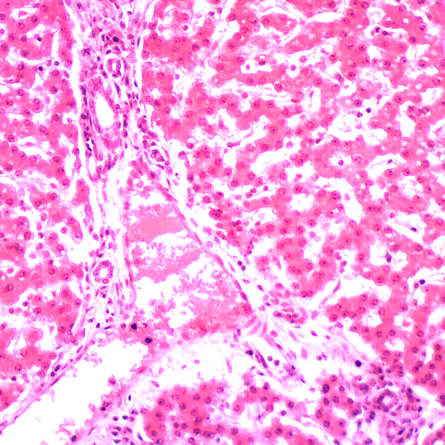

A Siendentopf head in either binocular or trinocular format is inclined at an ergonomic 30 degrees for more comfortable viewing. An optional ergonomic head offers 10 to 50 degrees of inclination range for even greater flexibility and viewing comfort. The head includes 10x Super Widefield High Eyepoint eyepieces F.N.22. Optional 15x and 20x eyepieces are available as is a High Eyepoint 10x focusable eyepiece that accepts 25mm reticles. The DIN Infinity Corrected Optical System (ICOS) includes four Semi Plan Apochramatic Phase Contrast objective lenses (PH4x, PH10x, PH40xS and PH100x oil), set in a ball bearing mounted, quintuple nosepiece.An 80/20 beam splitter is employed for photomicrography in the trinocular head (100% to eyetubes or 80% to phototube & 20% to the eyetube). Please note that you will need to purchase an appropriate trinocular adapter for your camera.